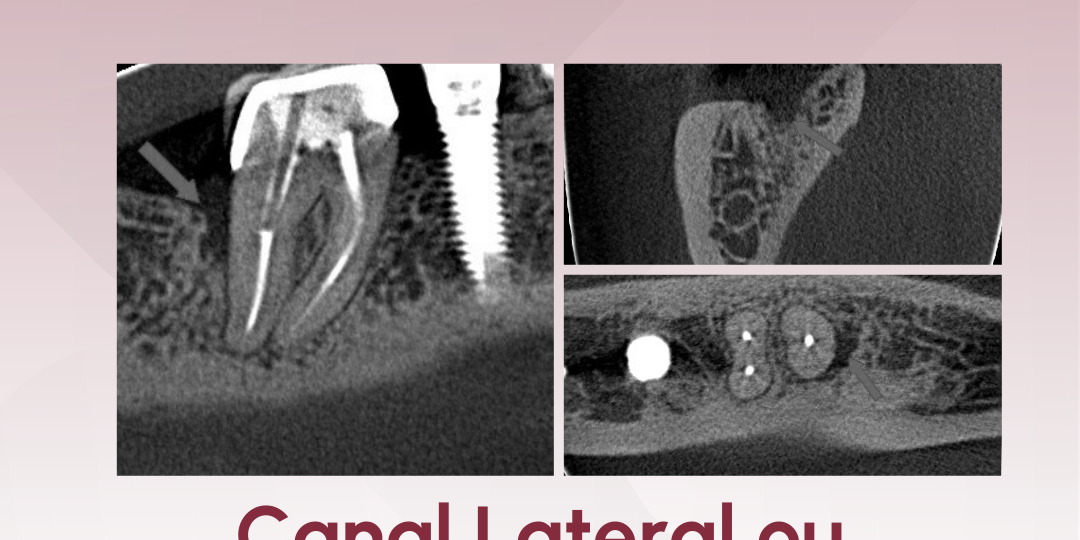

Ao navegarmos na tomografia, nos chamou atenção uma perda óssea angular na face distal do dente 47, em terço cervical de raiz (imagens 1 e 2).

Esse tipo de imagem nos faz pensar em uma fratura vertical devido às características e localização. Um tipo de fratura em que notamos um aumento considerável nos últimos anos.

Porém, ao realizarmos a navegação de maneira adequada, associando os 3 planos e trabalhando escala de cinza, foi possível localizar e diferenciar um canal lateral nesta região (imagens 3,4 e 5), e que, não por coincidência, sua saída está localizada no epicentro da reabsorção óssea.

Reabsorção óssea angular — face distal do 47

Padrão clássico de perda óssea angular

A princípio nos faz pensar em fratura vertical, porém como biologia não é matemática, precisamos analisar além do padrão.

Canal lateral visível nos três planos

O diagnóstico só foi possível com navegação detalhada e uso correto da escala de cinza.

Saída do conduto lateral coincide com a área de reabsorção óssea